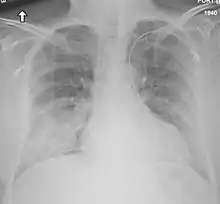

Medical imaging

Chest X-ray findings tend to show bilateral patchy infiltrates consistent with viral pneumonitis and acute respiratory distress syndrome (ARDS). Lower lobes tend to be more involved. CT scans show interstitial infiltrates.[28]